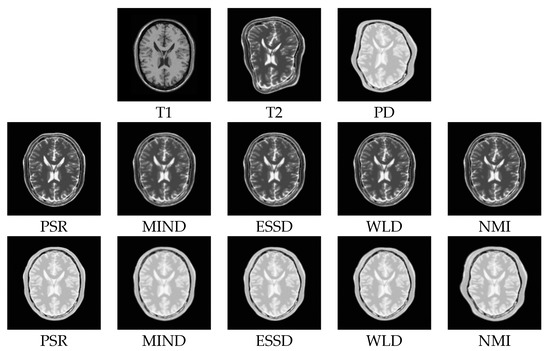

2.2. Structural Representation

3.2.1. Test on the BrainWeb Dataset